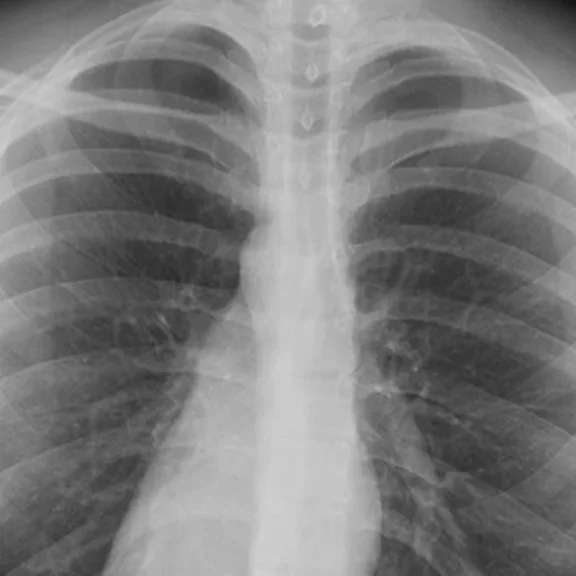

Healthy patient on the left, patient with SARS-CoV-2 on the right © Institut Pasteur